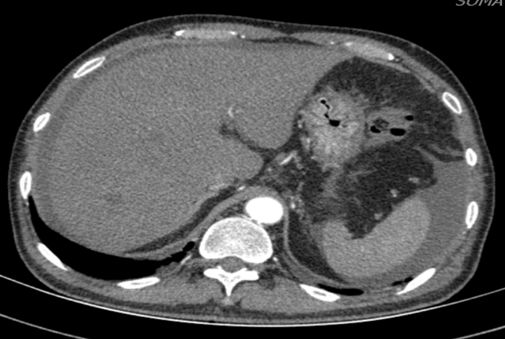

进一步检查及确诊:增强CT检查:下腔静脉肝段狭窄,内可见造影剂填充,肝脏异常强化(肝脏弥漫密度减低,门脉静脉期及平衡期显示肝脏不均匀强化,肝静脉周围呈片状明显强化,余肝实质呈轻度强化);腹部MRI:肝实质信号不均、肝静脉显示不清、腹水;肝脏病理活检:肝小叶结构未见异常,小叶中央为主的肝细胞片状退变坏死,灶性区域可见肝窦内淤血现象,形态提示缺血或淤血改变,致病因素包括药物/毒物、流出道梗阻(VOD、布加综合征)。免疫组化结果:CD34染色未见异常,CK7染色显示局部胆小管增生,局部肝细胞胆管化,HBsAg(-),特殊染色结果:Masson染色显示汇管区纤维组织增生,PAS、PAS+消化、铁、铜染色未见异常,网织纤维局部破坏。追问病史,患者起病前2月曾服用“三七粉”1月。最终诊断为吡咯生物碱相关性肝窦阻塞综合征。

CT: